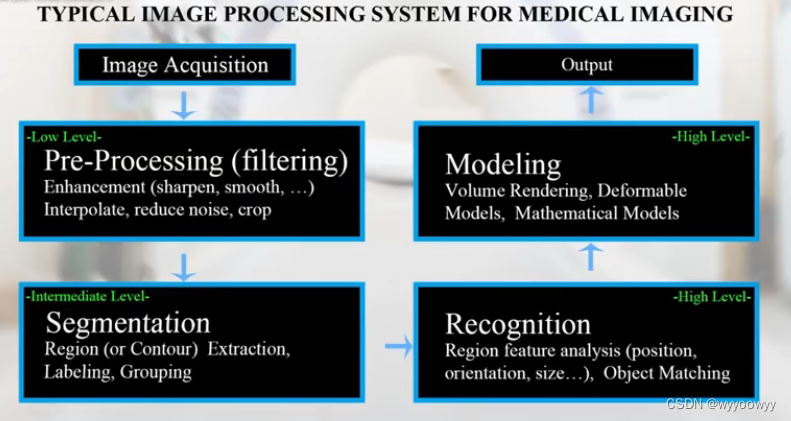

8、医学图像的处理流程

1、Low level : 图像滤波,图像的预处理

输入 : 图像,输出:图像

2、Intermediate level : 图像分割,输入:图像,输出:可能是分割后边缘的集合

3、High level :图像理解/模式识别 输入:符号集,输出:功能的表达

处理过程: